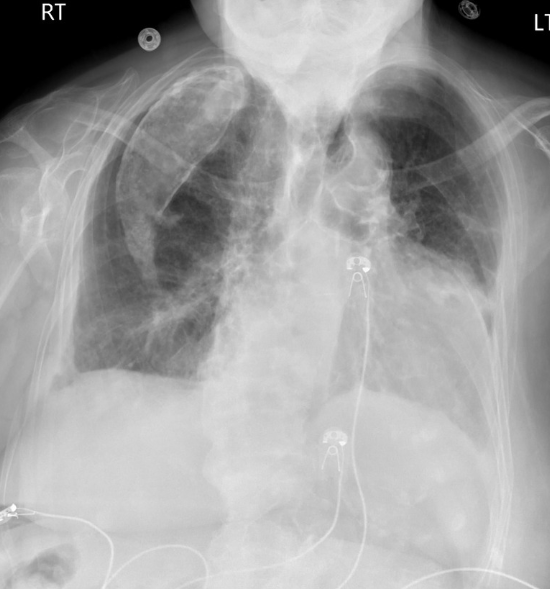

• Vieux traitement de la TBC

• On injectait de l’huile dans la plèvre pour comprimer le poumon

Imagerie

• Lésion pleurale calcifiée avec densités graisseuses

oleo oléo thorax oléothorax